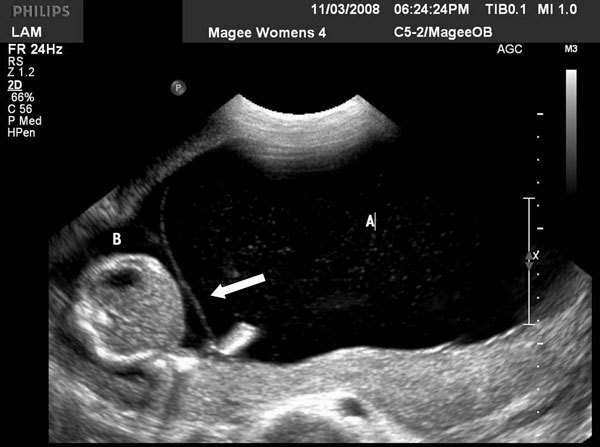

Como diagnosticar Sd Transfusão Feto-fetal?

USG vê POLIDRAMNIA em um feto e OLIGODRAMNIA em outro